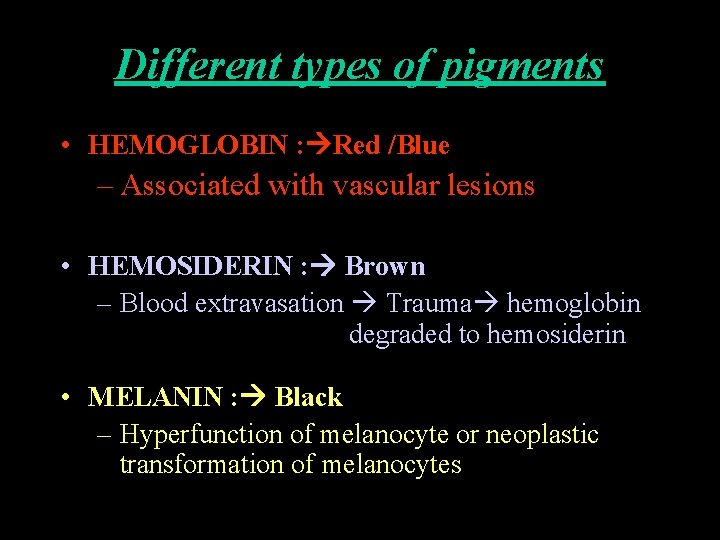

Different types of pigments • HEMOGLOBIN : Red /Blue – Associated with vascular lesions • HEMOSIDERIN : Brown – Blood extravasation Trauma hemoglobin degraded to hemosiderin • MELANIN : Black – Hyperfunction of melanocyte or neoplastic transformation of melanocytes